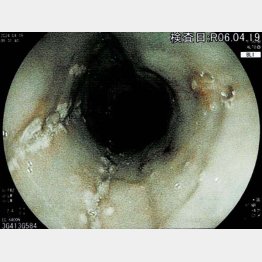

ところが内視鏡検査で、食道にカビが生えていることが判明(写真)。「とりあえず様子を見ましょうか」と言われたが、知り合いの医師に話したところ治療を勧められたため、改めて消化器科医に相談。カビの増殖を抑える薬を処方された。治療を終えた今は、胸のつかえなどの不調はすっかり消えているという。